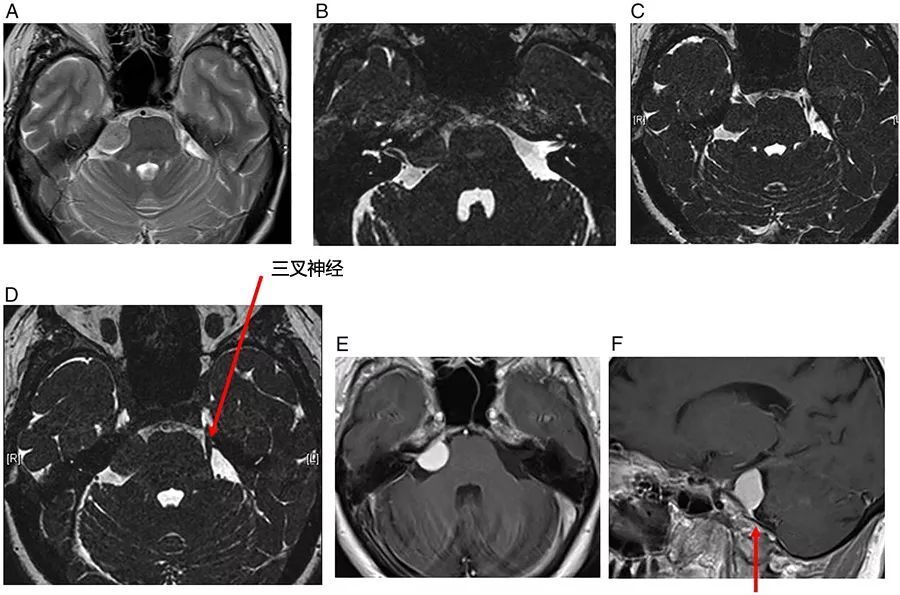

图9  乳腺癌所致恶性脑膜炎。可见左侧内听道强化肿物,类似于前庭神经鞘瘤,桥脑池中另可见一肿物,沿着左三叉神经的走行路径延伸

图10  右侧前庭神经鞘瘤。位于内听道基底部,向上延伸至耳蜗孔,病变随访3年以上未进展

图11  右侧面神经瘤。位于右侧内听道基底部,可见膝状神经节和内听道处强化肿物

图12  右侧舌咽神经/迷走神经鞘瘤。可见桥小脑角区域混杂信号的肿物,增强扫描可见显著强化,右侧小脑中脚受压变形,病灶向下延伸并进入颈静脉孔